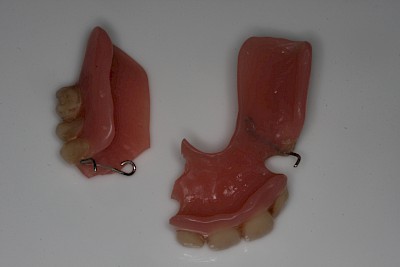

Hält eine Teilprothese kann es auch sein, dass das Verbindungselement defekt oder verlorengegangen ist. In diesen Fällen ist zu prüfen, ob eine Klammer abgebrochen oder ein Verbindungselement wie z. B. eine Krone fehlt. Ist dies der Fall muss ein Zahnarzt gerufen werden.